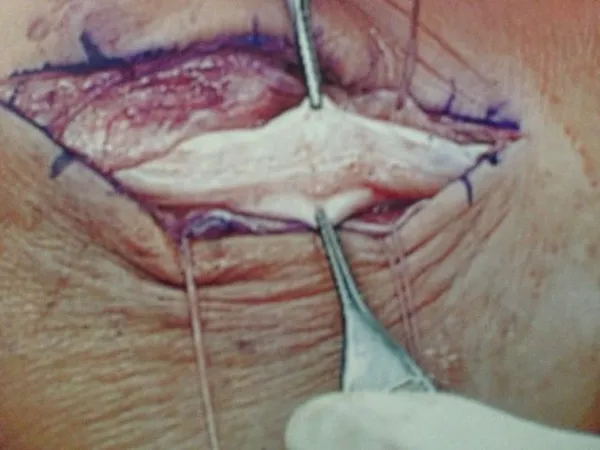

Below, Peroneal Tear with Low lying muscle belly. The muscle belly is removed and bulked to allow gliding and reduce congestion.

The muscle belly is seen at the right and closure of the sheath on the left and bottom pics.